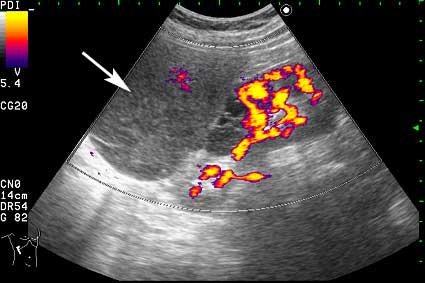

- Образование в режиме энергетического доплера.

Что-то прилегает или исходит из почки кпереди...

Нет, это кистоподобное образование, связанное с почкой.

Почечно-клеточный рак правой почки, кистозная форма.

Но только по густому содержимому кистозного компонента. Стенка тонкая, кровоток не прокрашивается (единичный мелкий срез сосуда в центре образования больше похож на артефакт, а м.б. им и является).

Если бы в этом случае и содержимое было бы более "жидким", вероятность постановки правильного диагноза была бы минимальной.